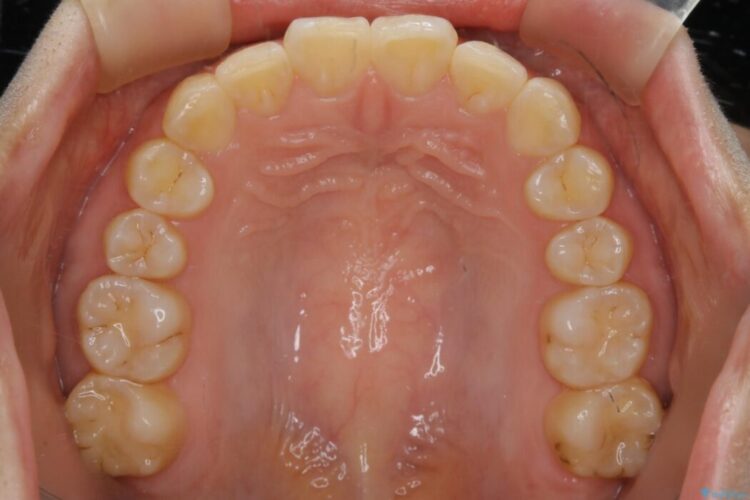

噛み合わせの違和感と前歯のガタガタを主訴に来院されました。

歯軸傾斜と軽度の叢生が見られましたので、通常の位置へと傾きを戻し少量の遠心移動に加えアーチ(歯列弓)の拡大とIPRを施すことで改善していく非抜歯での治療計画としました。